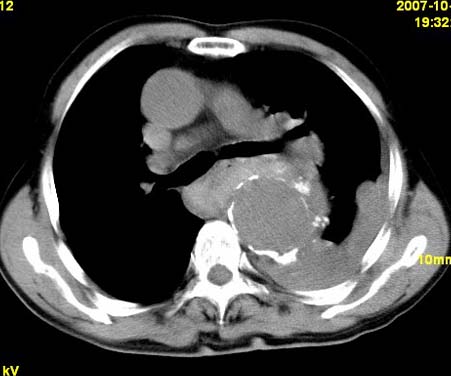

标题: CT10190:男,70,胸部疼痛数年,加重一天。典型病例。 [打印本页]

标题: CT10190:男,70,胸部疼痛数年,加重一天。典型病例。

典型降主动脉瘤伴血栓形成.瘤体下部局部边缘不清,结合病史,不除外局部撕裂外渗可能.另左侧胸水,肺部压迫不张改变.建议增强进一步检查.

1.降主动脉瘤伴血栓形成.2.左侧胸腔积液,考虑为主动脉瘤破裂所致。

降主动脉明显增粗,边缘模糊,周围低密度影,双侧胸膜腔少量积液,结合临床考虑胸主动脉瘤破裂并双侧胸腔积液。